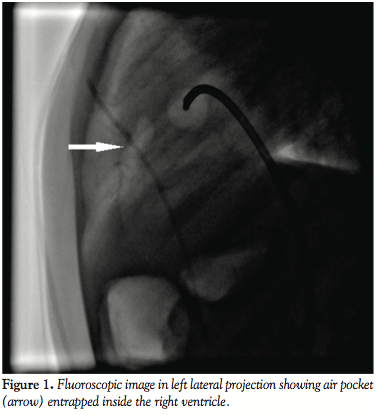

Under general anesthesia, vascular access was obtained from the right femoral vein and artery. The Swan-Ganz balloon flotation catheter was introduced into the right atrium. As soon as the catheter was inflated with room air, it burst and an air pocket was seen within the right ventricle (Figure 1; Video 1) resulting in “air lock,” or venous air embolism. Within fractions of a second the patient’s blood pressure started falling and arterial saturation dropped to 50%. The cardiac monitor showed sinus tachycardia with gross ST segment elevation and hypotension (mean blood pressure 36mm Hg; Figure 2A). Immediately, we started high flow oxygen and we planned to aspirate the air. A 6 Fr angiographic catheter (Berman) was introduced into the right ventricle and directed toward the air pocket, and manual aspiration (Video 2) was initiated. During the process of aspiration, a few smaller bubbles embolized into the pulmonary and systemic circulation (via large nonrestrictive VSD and overriding aorta), however we aspirated the majority of the air. As soon as the air was aspirated blood pressure dramatically improved, tachycardia improved, and ST elevation settled (Figure 2B).